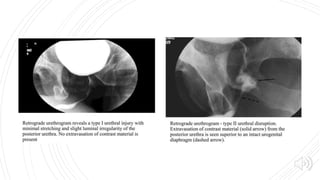

ANTERIOR URETHRAL TRAUMA  Mechanism  Iatrogenic(attempted catheterization, instrumentation )  Blunt perineal trauma (straddle injury) : bulbar urethra and corpus spongiosum are compressed against the inferior aspect of anterior pelvic ring

FINDINGS Rupture Partial : contrastextravasation with some filling of proximal urethra Complete : failure of filling of proximal urethra Stricture (usually <1cm or so in length).